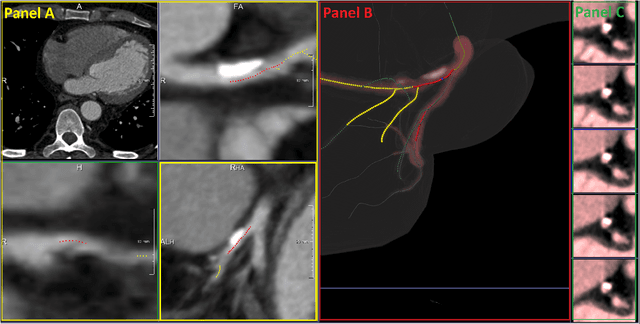

Abstract:We propose a fully automated algorithm based on a deep-learning framework enabling screening of a Coronary Computed Tomography Angiography (CCTA) examination for confident detection of the presence or complete absence of atherosclerotic plaque of the coronary arteries. The system starts with extracting the coronary arteries and their branches from CCTA datasets and representing them with multi-planar reformatted volumes; pre-processing and augmentation techniques are then applied to increase the robustness and generalization ability of the system. A 3-Dimensional Convolutional Neural Network (3D-CNN) is utilized to model pathological changes (e.g., calcification) in coronary arteries/branches. The system then learns the discriminatory features between vessels with and without atherosclerosis. The discriminative features at the final convolutional layer are visualized with a saliency map approach to localize the visual clues related to atherosclerosis. We have evaluated the system on a reference dataset representing 247 patients with atherosclerosis and 246 patients free of atherosclerosis. With 5-fold cross-validation, an accuracy = 90.9%, with Positive Predictive Value = 58.8%, Sensitivity = 68.9%, Specificity of 93.6%, and Negative Predictive Value = 96.1% are achieved at the artery/branch level with a threshold of 0.5. The average area under the curve = 0.91. The system indicates a high negative predictive value, which may be potentially useful for assisting physicians in identifying patients with no coronary atherosclerosis that need no further diagnostic evaluation.